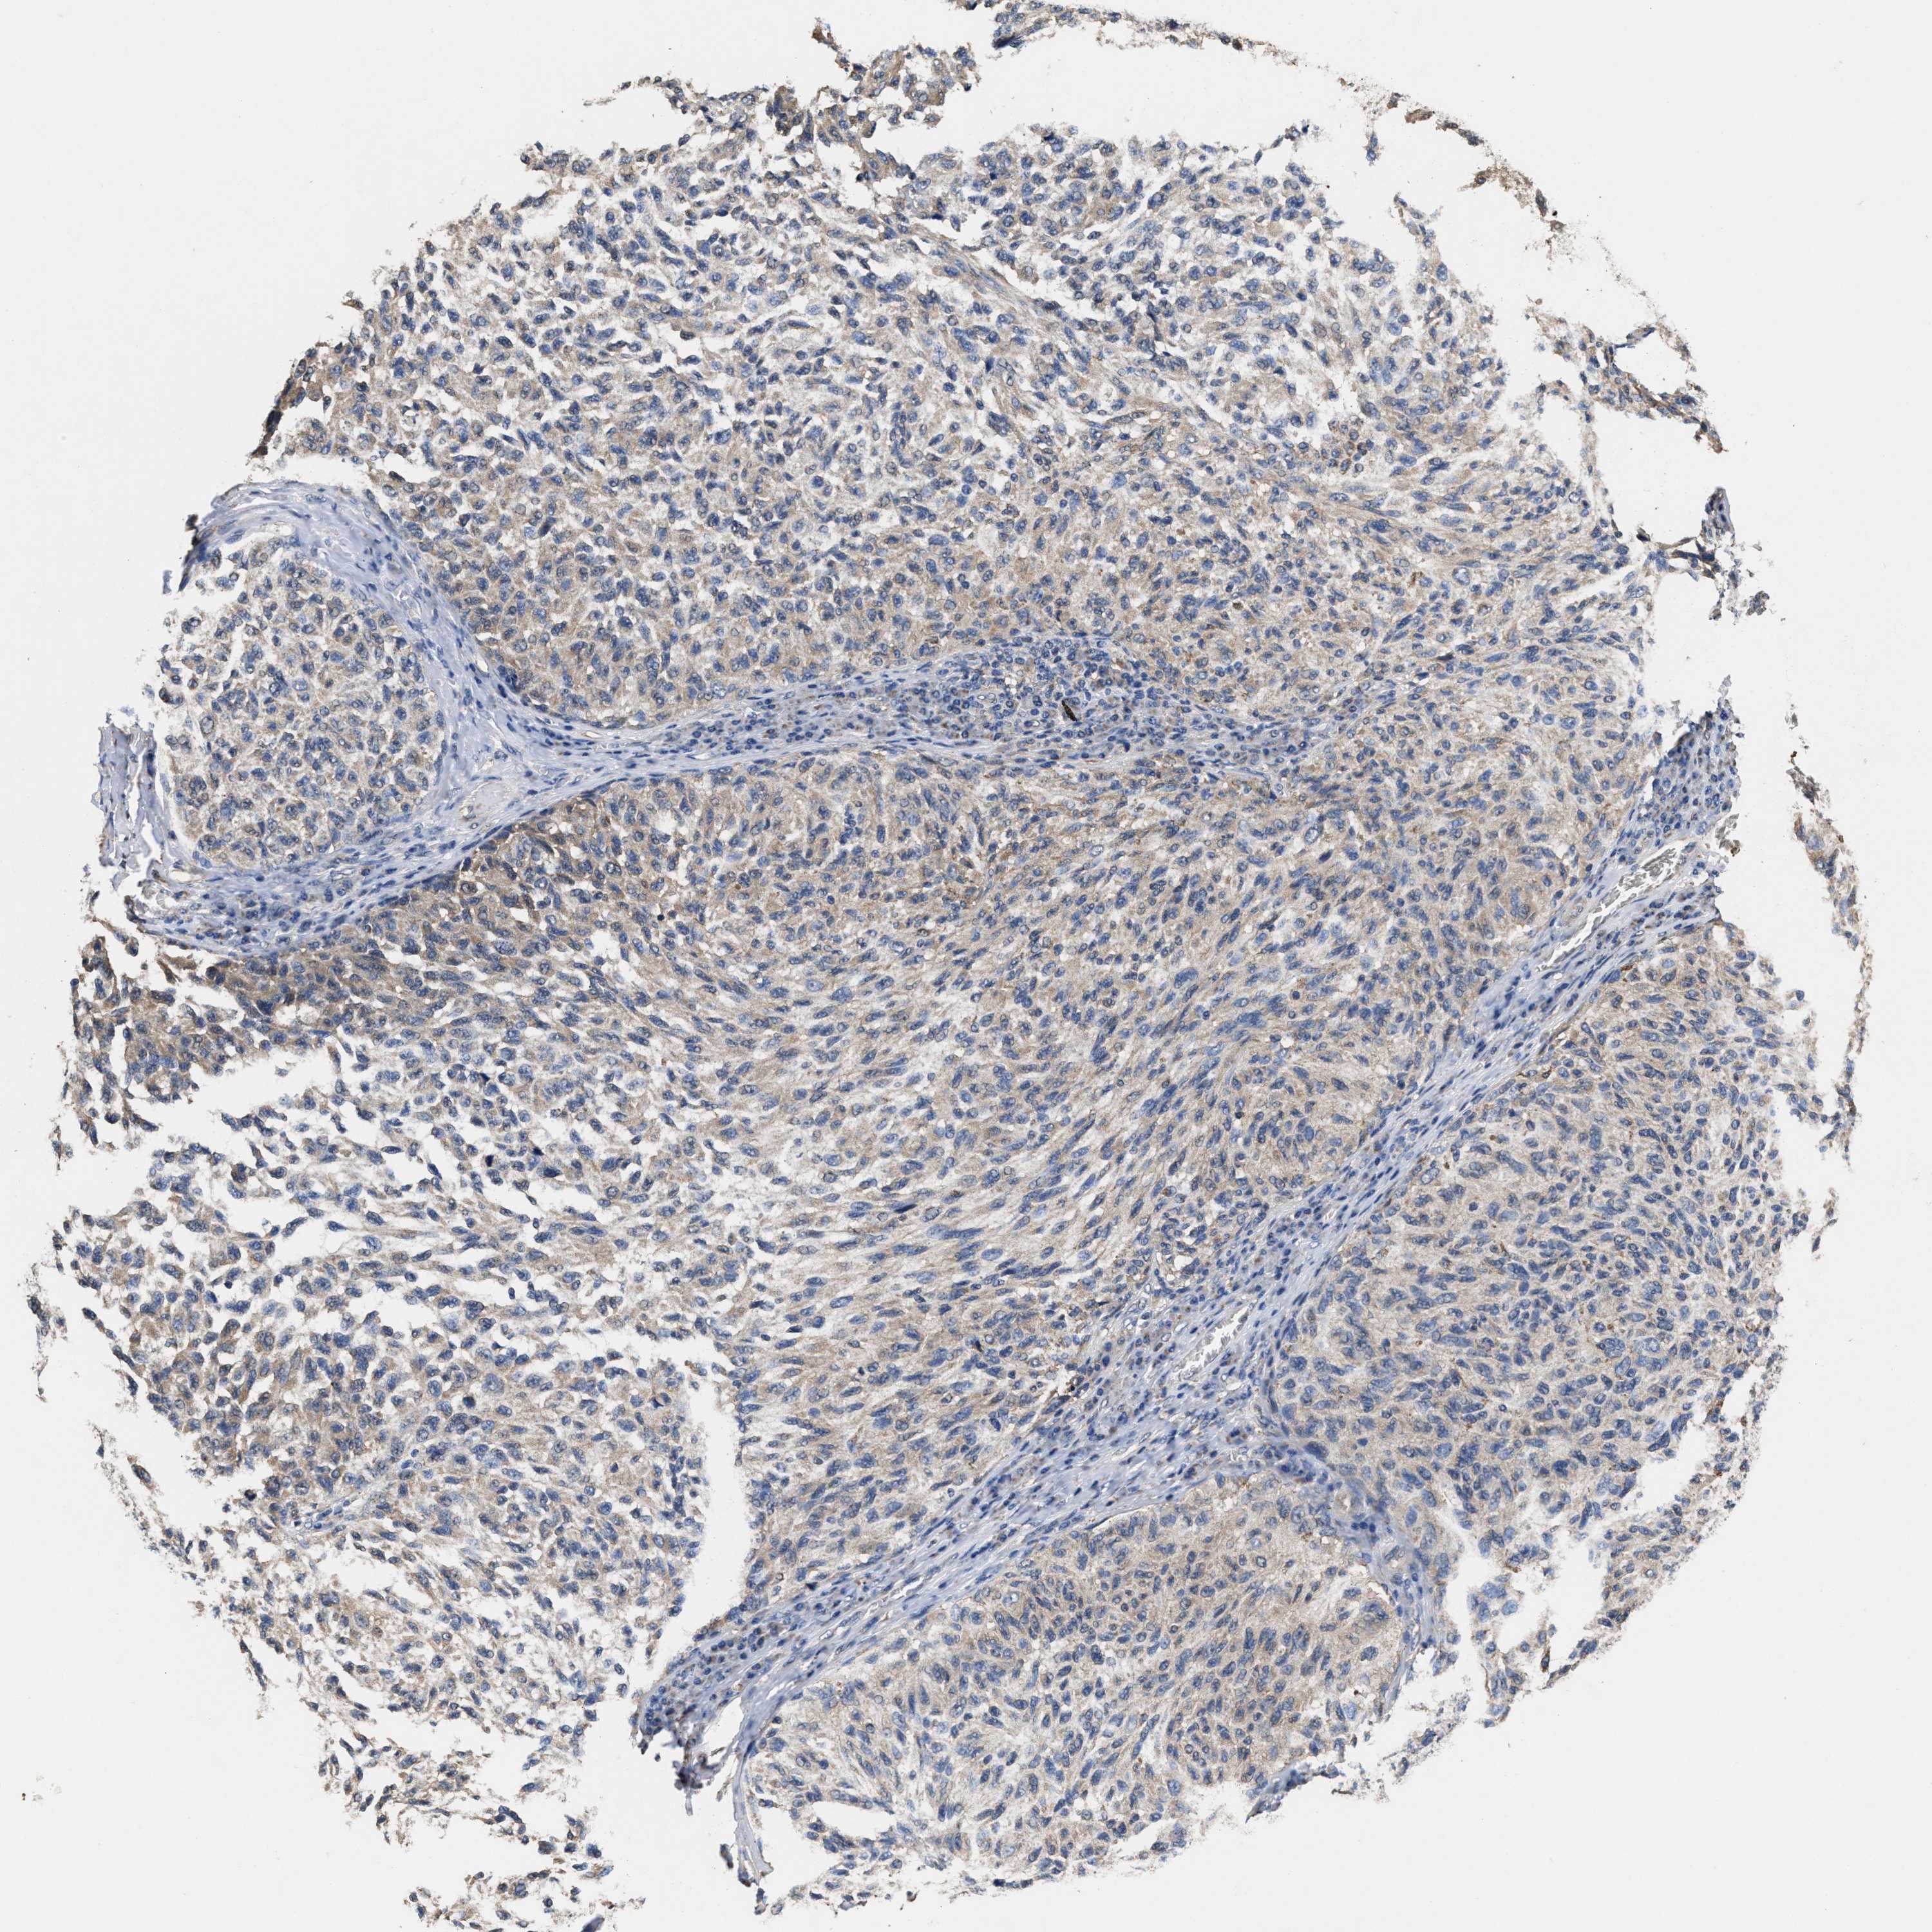

MELANOMA - Protein expressioni

A mouse-over function shows sample information and annotation data. Click on an image to view it in a full screen mode. Samples can be filtered based on level of antibody staining by selecting one or several of the following categories: high, medium, low and not detected. The assay and annotation is described here.

Note that samples used for immunohistochemistry by the Human Protein Atlas do not correspond to samples in the TCGA dataset.

Antibody stainingi

Antibody staining in the annotated cell types in the current human tissue is reported as not detected, low, medium, or high, based on conventional immunohistochemistry profiling in selected tissues. This score is based on the combination of the staining intensity and fraction of stained cells.

Each image is clickable and will lead to virtual microscopy that enables deeper exploration of all samples and also displays staining intensity scores, fraction scores and subcellular localization as well as patient and tissue information for each sample.

Malignant melanoma, NOS

Malignant melanoma, Metastatic site